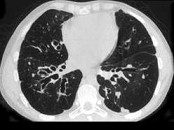

- 单项选择题男,18岁, 咳嗽,咳痰, 咯血半月余,CT检查如图, 最可能的诊断是 ( )

A、过敏性肺炎

B、支气管扩张

C、原发性肺结核

D、大叶性肺炎

E、肺癌